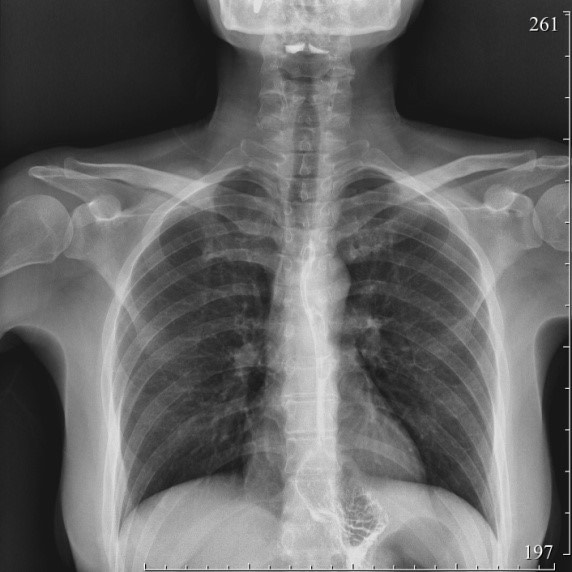

2186. Около 7 лет назад пациентке 48 лет выполнена лапароскопическая фундопликация, при полипозиционной рентгеноскопии пищевода и желудка определяют